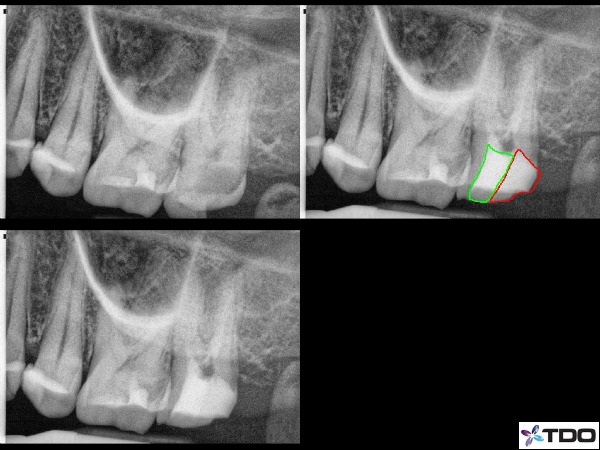

I can think of just a couple of disadvantages to performing this service. Firstly, this certainly does lengthen the treatment time. Additionally, I also find some of these pre-endodontic build-ups to be more difficult than the RCT itself (figure 4). But as with anything, the more you do it, the easier it becomes. Developing comfort with the various systems takes time as well. We use many techniques to restore these areas, common in many dental offices. There are a variety of devices to hold the material in place including copper bands, several matrix systems, and even gingival block out materials. All prove very effective. To control tissue we use the electrosurg, hemostatic agents, and commonly the System B endodontic heat tip at a high temperature.

Fig. 4: Here is a case I started RCT on today (4/3/13 and thus no completion x-ray as the patient returns in a couple weeks for the finishing appointment). But this patient has a very small mouth and the decay was involving the distal and distal-buccal walls. Getting great isolation and no contamination with the location of decay and with a limited mouth opening was tough. In this case the pre-endodontic build-up took about twice as long as the shaping and irrigation of the canal spaces (4 canals). There is calcium hydroxide in the canals currently. Red indicates the general location of the pre-endo build-up and the green is a temporary restorative material in the access point.